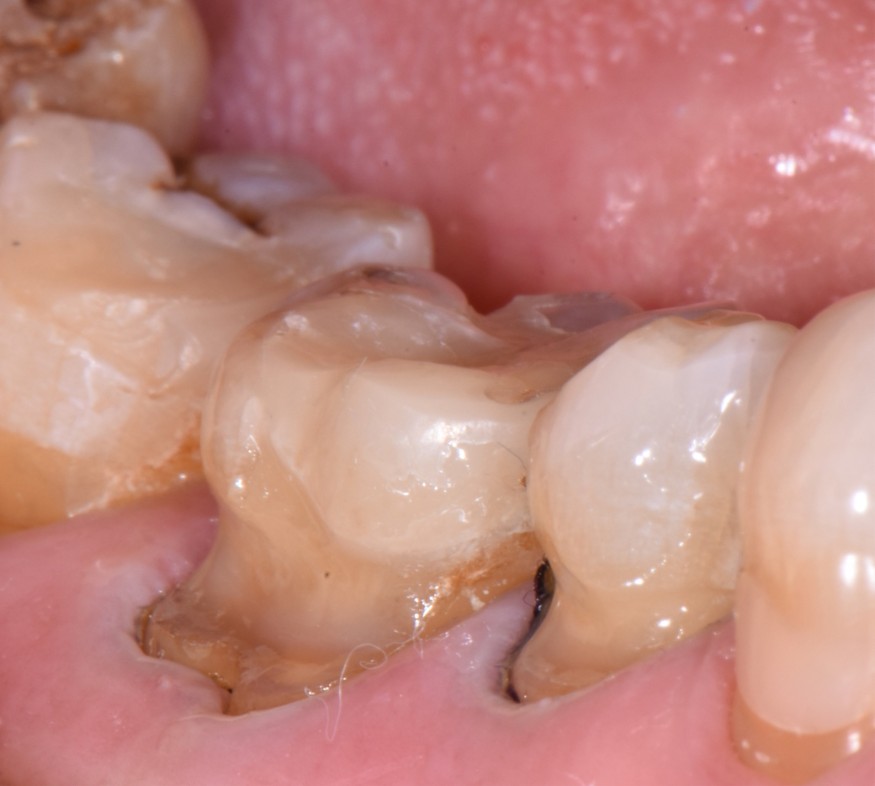

- Exposition dentinaire, due à la perte d’émail ou de cément, par abrasion (brossage traumatique), érosion (acides), attrition (bruxisme) (fig. 3-7), ou anomalies de structure (MIH**, amélogenèse imparfaite) [5].

(Crédit photo : Olivia Kérourédan) - Figure 6. Lésions d’usure typiques provoquées par des phénomènes d’abrasion.

(Crédit photo : Olivia Kérourédan) - Figure 7. Asymétrie des lésions érosives constatée chez une patiente souffrant de reflux gastro-œsophagiens.